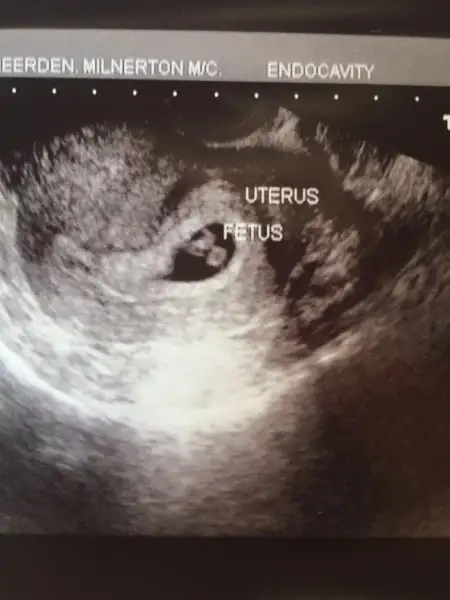

Kızlar banada cevap verin yaa 8 haftalık hali vajinal muayene ile çekilmişti